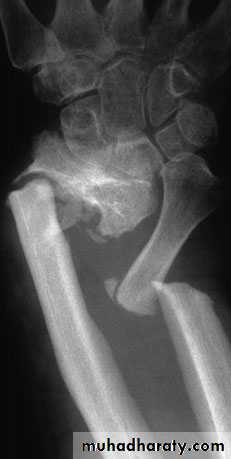

Radiological diagnosis;

The fr line can be shown by a good x-ray exam. specially with application of the role of two, the fr line can be seen and we can describe the fr site, shape and displacement exactly.

Sometimes bone unites in an abnormal position, this is called MAL-UNION, this can lead to various deformities and functional impairments.